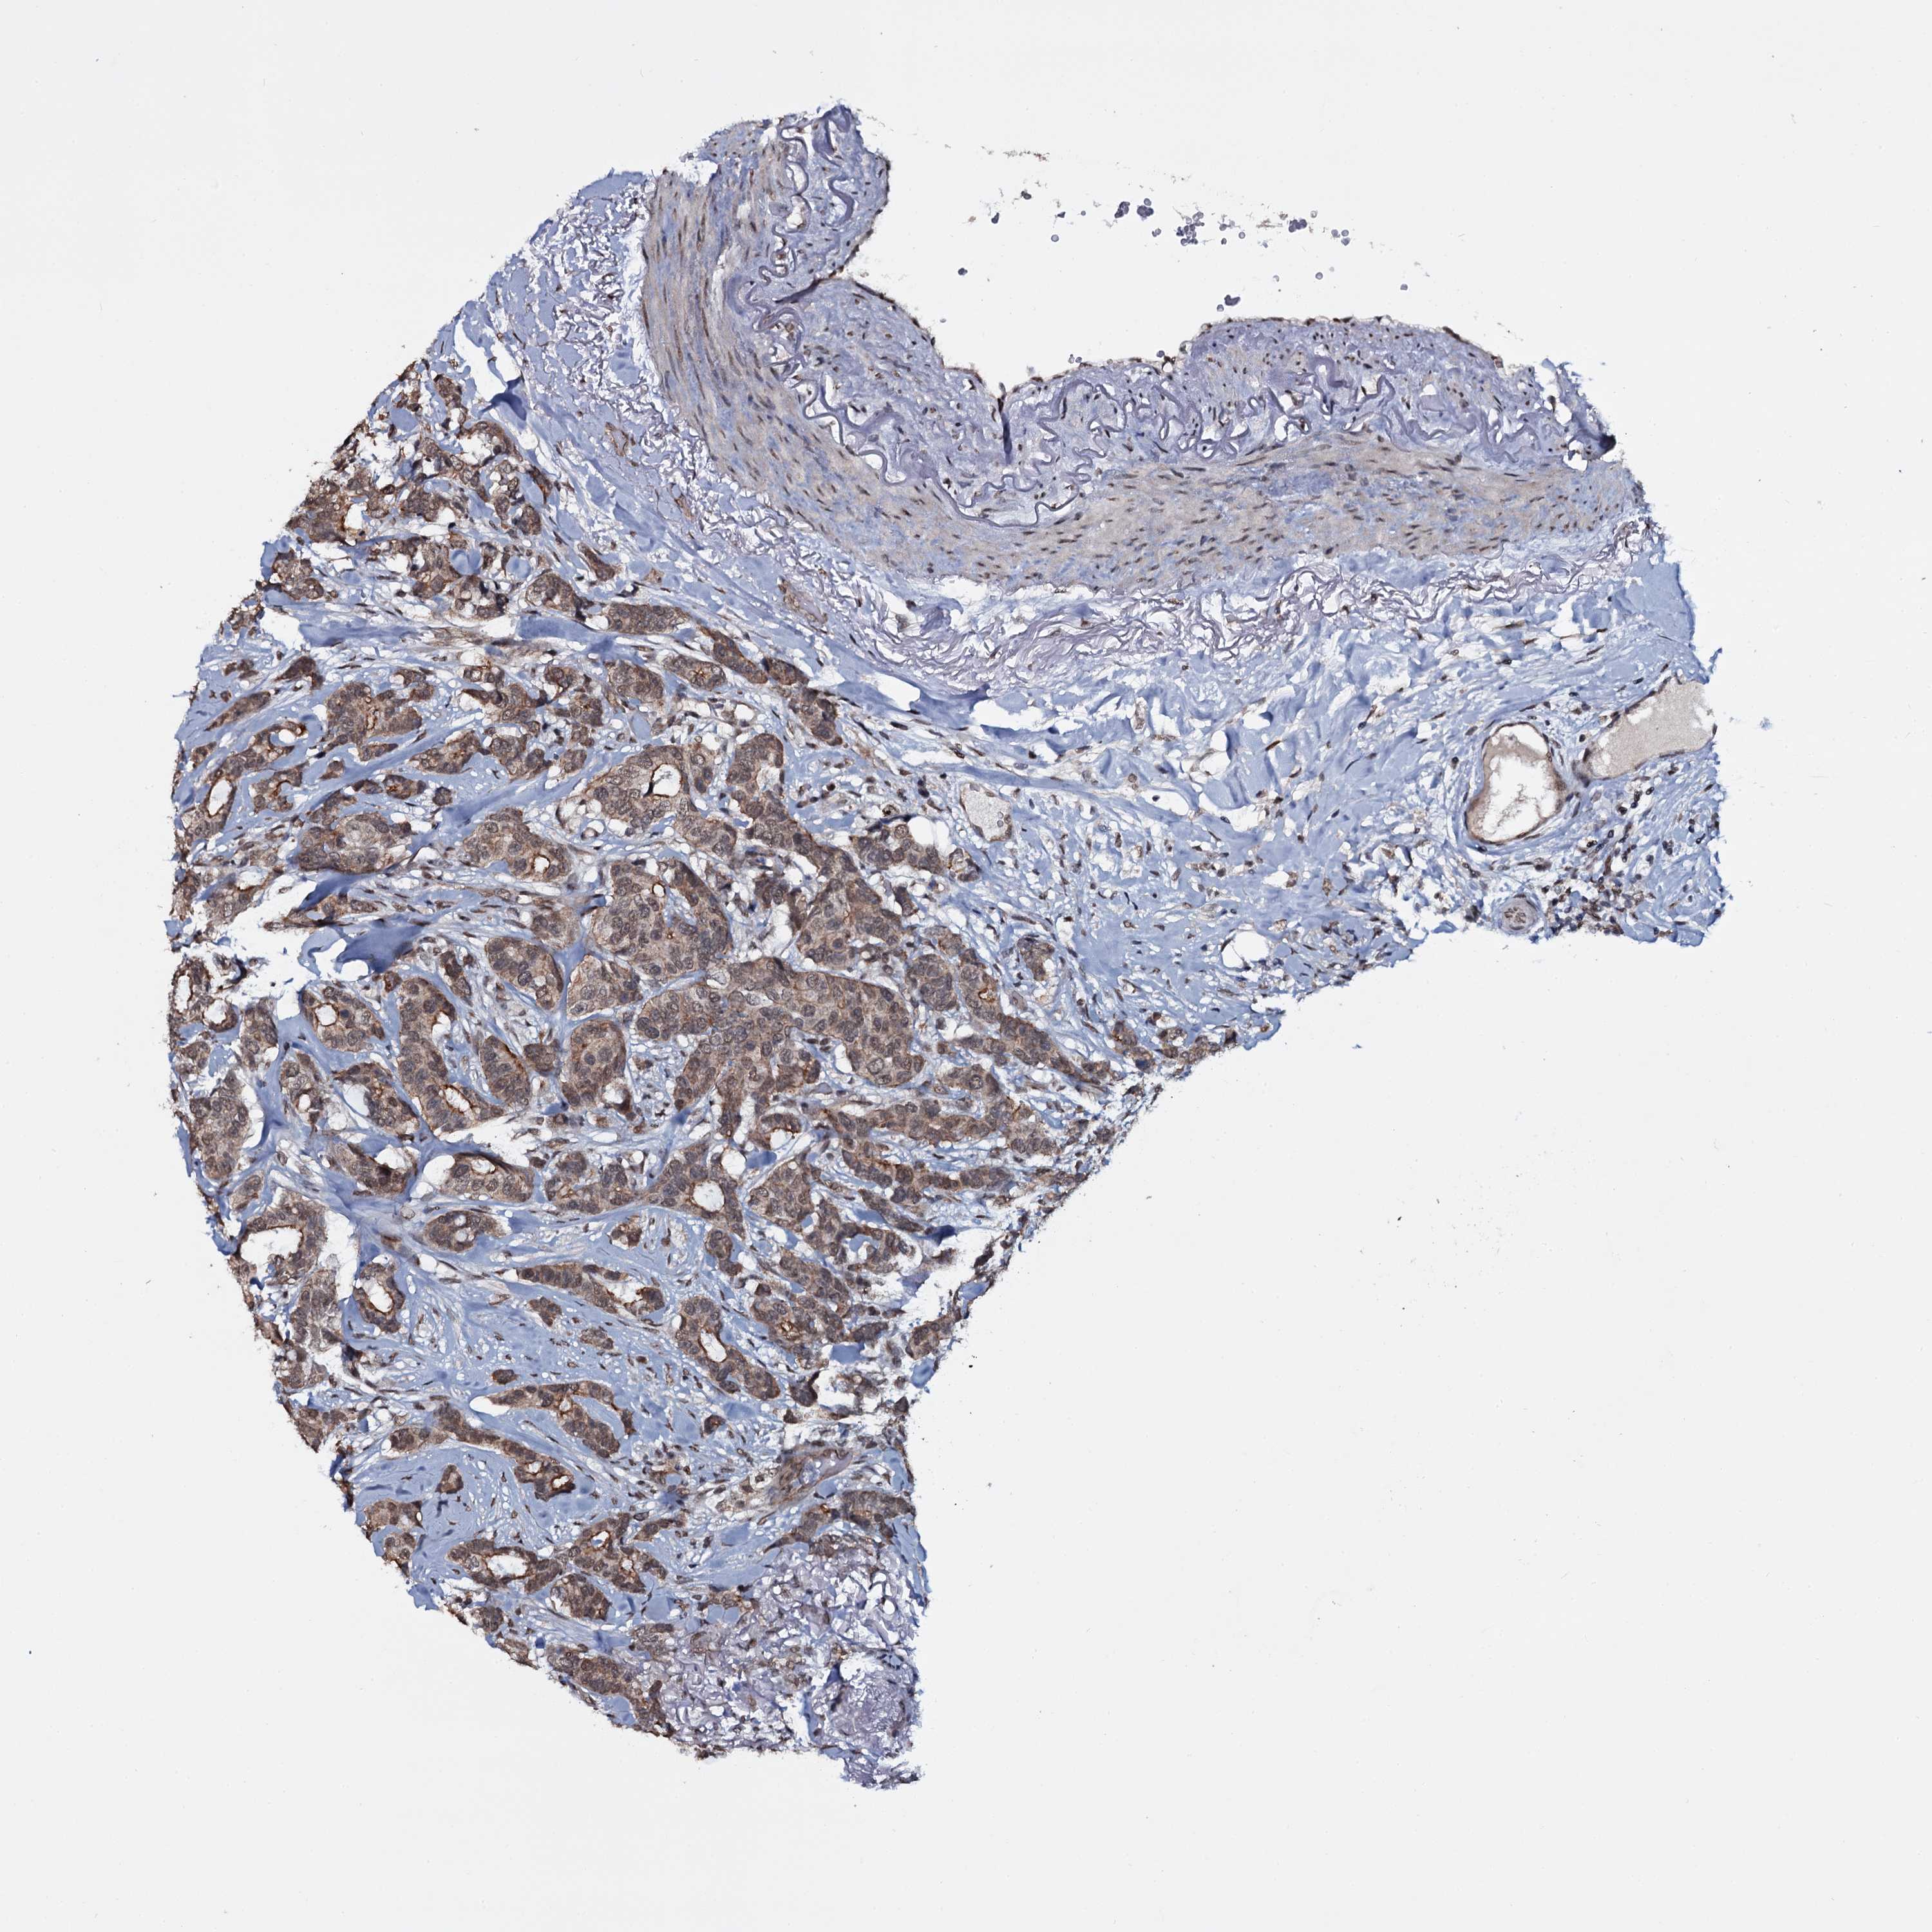

CANCER BREAST CANCER Show tissue menu

BRCA TCGA BRCA VALIDATION PROTEIN EXPRESSION